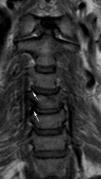

Las técnicas de imagen proporcionan una imagen anatómica excelente de la columna cervical. La elección de cada una de ellas dependerá del escenario clínico y de las alternativas terapéuticas. La radiografía simple sigue siendo fundamental, ya que permite valorar la alineación, las alteraciones óseas y el seguimiento tras el tratamiento. La mayor resolución de contraste de la resonancia magnética permite la valoración de las partes blandas, incluyendo los discos intervertebrales, los ligamentos, la médula ósea y la médula espinal. El papel de la tomografía computarizada en el estudio de la patología degenerativa ha cambiado en los últimos tiempos debido a la gran resolución espacial y su capacidad para visualizar el componente óseo.

Imaging techniques provide excellent anatomical images of the cervical spine. The choice to use one technique or another will depend on the clinical scenario and on the treatment options. Plain-film X-rays continue to be fundamental, because they make it possible to evaluate the alignment and bone changes; they are also useful for follow-up after treatment. The better contrast resolution provided by magnetic resonance imaging makes it possible to evaluate the soft tissues, including the intervertebral discs, ligaments, bone marrow, and spinal cord. The role of computed tomography in the study of degenerative disease has changed in recent years owing to its great spatial resolution and its capacity to depict osseous components.